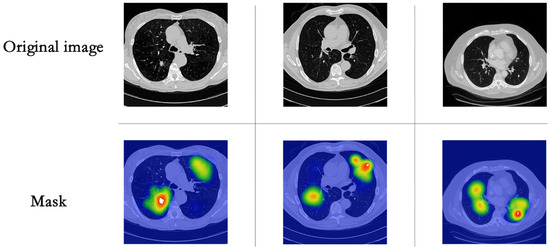

4.1. Data and Pre-Processing of Data